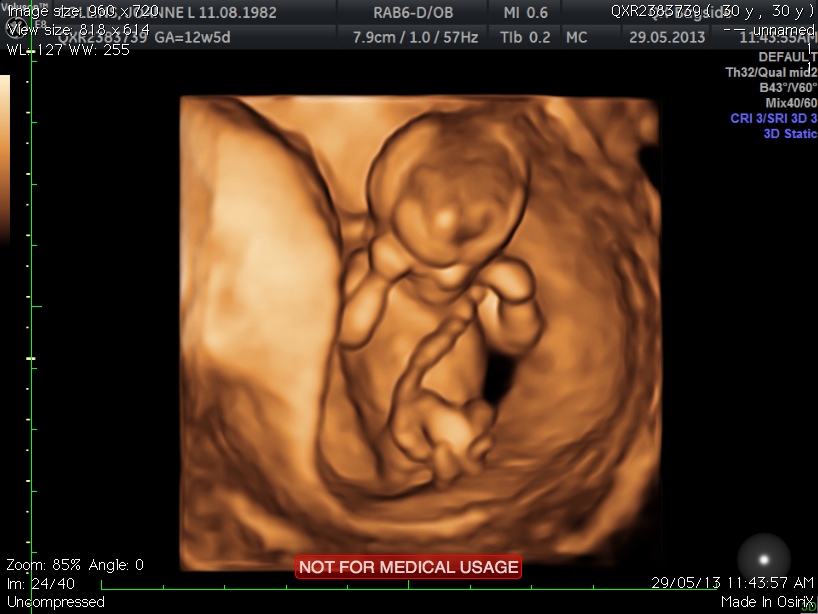

Ok so I have posted before and this is truly driving me crazy. I have 40 scan pics altogether and am constantly looking through them. So just now I have come across something which I would like to get your opinions on please. Ok so I'll post some pics now and explain what I'm wondering. So this pic is the one that everyone has been guessing on and had some girl and some boys guesses - more recently more boy guesses. So my question is - Is the white line you can see actually the nub? The reason for me asking is please look at the 4d pic in the second pic below (this pic is taken within 1 minute of pic 1) - the cord is wrapped around the leg - around the leg on the side at which the profile pic is taken. So my question is - Could the white line at at the top actually be the cord as in pic 2 and the nub is actually the one i have circled in pic 3 posted below? Hope this makes sense and you get where I'm coming from :) Thanks for reading x

Pic 2 - 4d of cord wrapped round leg

Attachment 11920